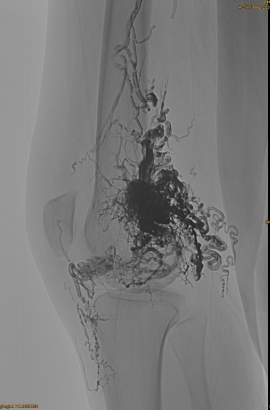

DSA inicial:

Resultat final:

Difícilment cap sortida venosa:

Fase tardana, un altre EMBO necessari, però molt millor: